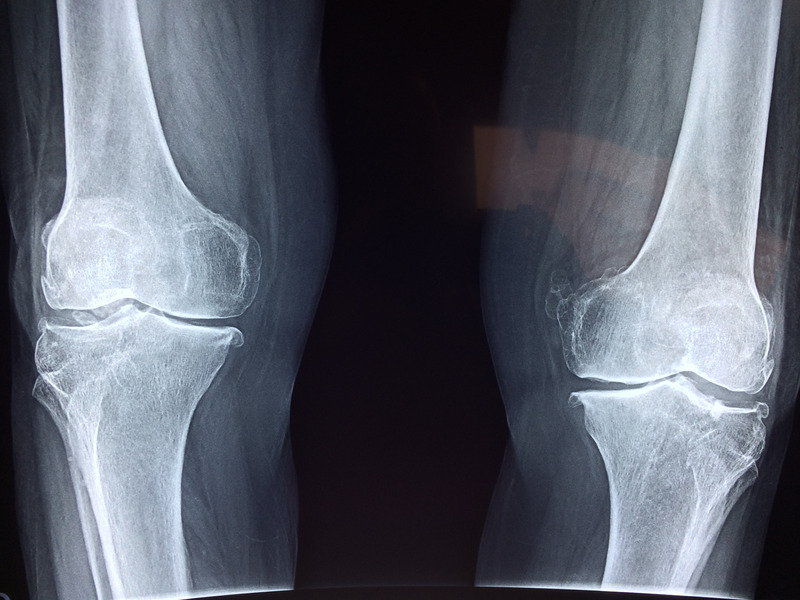

- Ефективно средство при остеоартрит и ставни проблеми

За разлика от много хранителни добавки, при които лиспват доказателства, че действат, N-Acetyl D-Glucosamine (N-A-G) е ефективен при остеоартрит.

За разлика от много хранителни добавки, при които лиспват доказателства, че действат, N-Acetyl D-Glucosamine (N-A-G) е ефективен при остеоартрит.

Едно от най-големите клинични проучвания, включващо близо 1600 потребители с болезнен остеоартрит в коляното, показва, че дори и само след няколко дни на прием се съобщава за намаляване на болката и подобряване на състоянието. Стимулирайки производството на хиалуронова киселина, N-Acetyl D-Glucosamine (N-A-G) стимулира функцията на ставите.